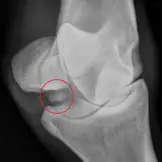

Die häufigste Indikation für eine Arthroskopie ist die Entfernung von Osteochondralen Fragmenten (Osteochondrosis dissecans / OCD/ Chip) bzw. Absplitterungen aus dem Gelenk und der Glättung von Knorpelschäden, welche als Folge dieser auftreten können. Diese sogenannten Chip- Operationen werden durchgeführt, wenn klinische Beschwerden wie Gelenkserguss und / oder Lahmheit aufgrund eines Chips auftreten. Aufgrund der hohen Qualitätsanforderungen, welche heutzutage mit der Vermarktung von Sportpferden einhergehen werden viele Pferde auch im Vorfeld des Verkaufs einer Chipoperation unterzogen werden. Ziel hierbei ist zum einen die Vermarktungschancen zu verbessern und andererseits eventuelle Gelenkschäden durch Reibung der Chips im Gelenk zu vermeiden und damit eine anhaltende Gesunderhaltung des Athleten zu gewährleisten.

Am häufigsten werden Chips im Huf-, Fessel- Sprung- und Kniegelenk gefunden und operiert. Wir bieten aber auch die arthroskopische Entfernung von Knochenfragmenten im Kron-, Carpal-, Ellbogen- und Schultergelenk an.